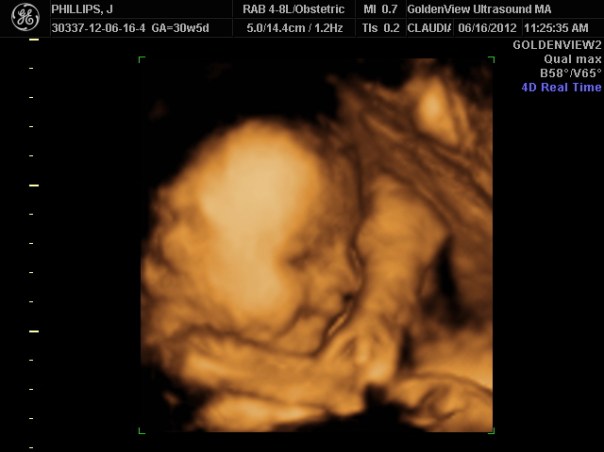

Each appointment after that was heart wrenching. We quickly learned our beautiful baby was a girl with no obvious genetic conditions. Monthly ultrasounds showed issues with her heart, then her kidneys, then her spine. We were sent to Boston for an MRI and more invasive ultrasounds and echoes. My baby was a fighter. I was put on bedrest and medication to control my blood pressure while we tried to avoid a premature birth like we experienced with her older sister. We met with doctors every week, had up to 3 ultrasounds a week. We learned at 35 weeks that she had stopped growing and was anticipated to weigh only 4pounds at birth. Following a non-reassuring ultrasound at 36 weeks where baby didn’t move, we were admitted to the hospital.

At 37 weeks via emergency c-section, Emilia Katherine Hope was born at 4:57pm weighing just 5 pounds and 18 inches long. We learned she had additional medical complications that weren’t seen in utero and a diagnosis of VACTERL association was confirmed based on this new information.